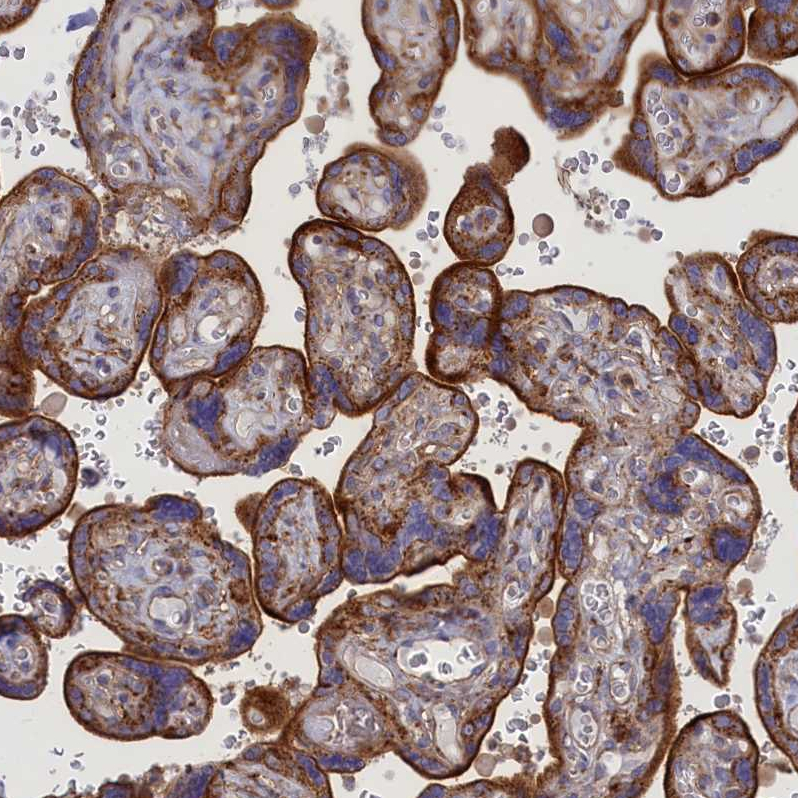

Immunohistochemical staining of human fallopian tube shows strong cytoplasmic positivity in glandular cells.